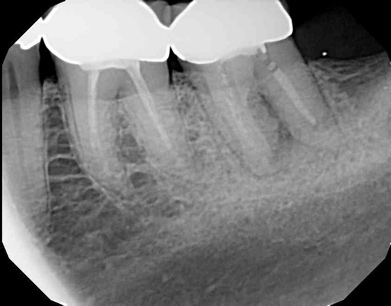

Fig 4.  Due to reported allergies to resin-based materials and eugenol, obturation was completed with a calcium hydroxide-based sealer (Figure 4 and Figure 5) with healing noted at a 1-year follow-up (Figure 6).

Figure 4

Fig 5.  Due to reported allergies to resin-based materials and eugenol, obturation was completed with a calcium hydroxide-based sealer (Figure 4 and Figure 5) with healing noted at a 1-year follow-up (Figure 6).

Figure 5

Fig 6.  Due to reported allergies to resin-based materials and eugenol, obturation was completed with a calcium hydroxide-based sealer (Figure 4 and Figure 5) with healing noted at a 1-year follow-up (Figure 6).

Figure 6